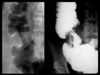

What is this finding?

What is it d/t?

Apple core sign

Colon adenocarcinoma